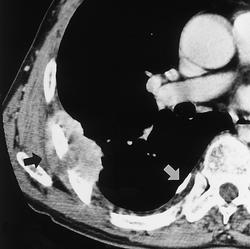

Асбест 1 КТ

Асбест 2 CTa

Дата: 06/02/2004

Просмотров: 541

Асбест 2 CTb

Просмотров: 504

Асбест 2 CTc

Просмотров: 597